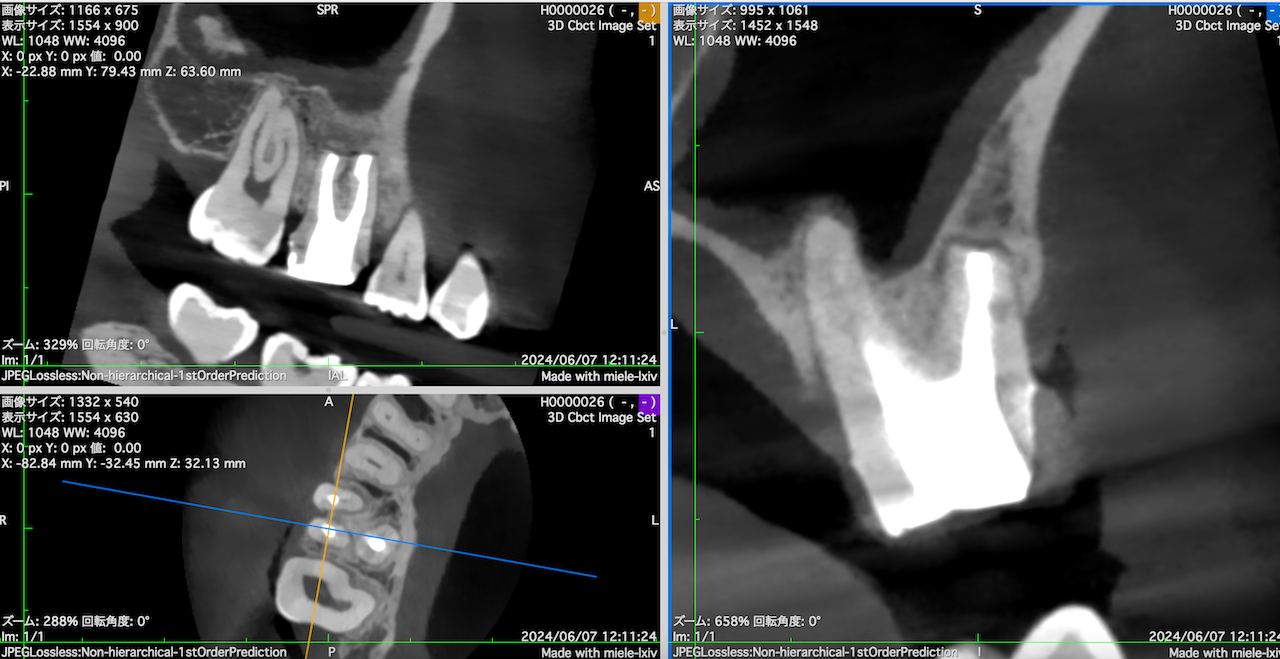

まずみえる絵を作成していただき、以下のような絵を作成してもらう。

CBCTを立ち上げると以下のような絵になるがこれでは何もわからない。

この絵を以下のような絵にしていく。

#3のMB,DB両方に病変がある。

これを分析しなければならない。

私は日々の臨床でそれを即座に見える絵にし、そして絵を分析し、

Apicoectomyが容易か、普通か、困難かを瞬く間に判定している。

その時間は数分だ。

短時間でその判定ができなければ、Apicoectomyという名のリングには立てないのだ。